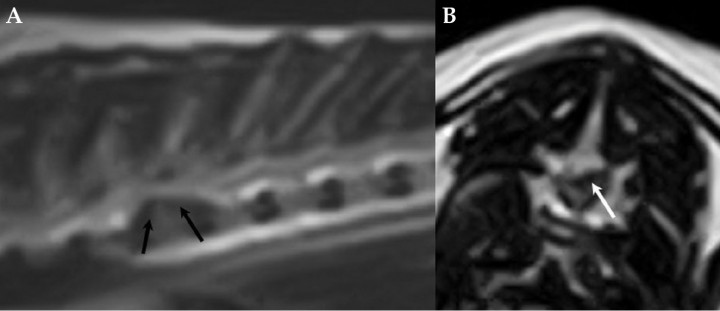

<p>Imágenes de resonancia magnética ponderada en T2W. (<strong>A</strong>) Imagen sagital. (<strong>B</strong>) Imagen transversal. Se aprecia una masa en continuidad dorsal con el cuerpo de T6 (flecha).</p>

Imágenes de resonancia magnética ponderada en T2W. (A) Imagen sagital. (B) Imagen transversal. Se aprecia una masa en continuidad dorsal con el cuerpo de T6 (flecha).